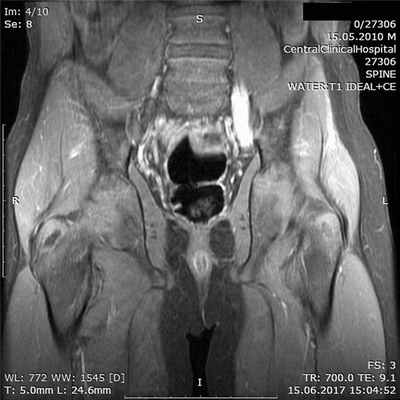

Результаты осмотра, УЗИ периферических нервов и ЭМГ констатировали поражение на уровне пояснично-крестцового сплетения. Для уточнения причины изменений проведено МРТ с контрастным усилением гадолинием, обнаружено увеличение нервных стволов и накопление контрастного вещества в пояснично-крестцовом сплетении (рис. 2). Рис. 2. Тот же пациент. МРТ пояснично-крестцового сплетения в режиме Т1 с контрастным усилением гадолинием. МРТ плечевого сплетения не выявило изменений.

В соответствии с алгоритмом обследования пациентов с подозрением на ХВДП проведено исследование ЦСЖ, которое не выявило белково-клеточной диссоциации; также не обнаружено антител к ганглиозидам периферических нервов в сыворотке крови.

На основании течения болезни (более 8 нед), данных МРТ — накопление контрастного вещества нервными стволами, результатов ЭМГ, указывающих на вовлечение пояснично-крестцового сплетения, предположено наличие дизиммунного процесса периферической нервной системы. Назначена комбинированная патогенетическая терапия 4 курсами с интервалами 1 мес: метилпреднизолон 3000 мг (суммарная доза на 1 курс) внутривенно и внутривенные иммуноглобулины в дозе 2 г на 1 кг массы тела в первый курс и 1 г на 1 кг массы тела в следующие 3 инфузии без последующей поддерживающей терапии.